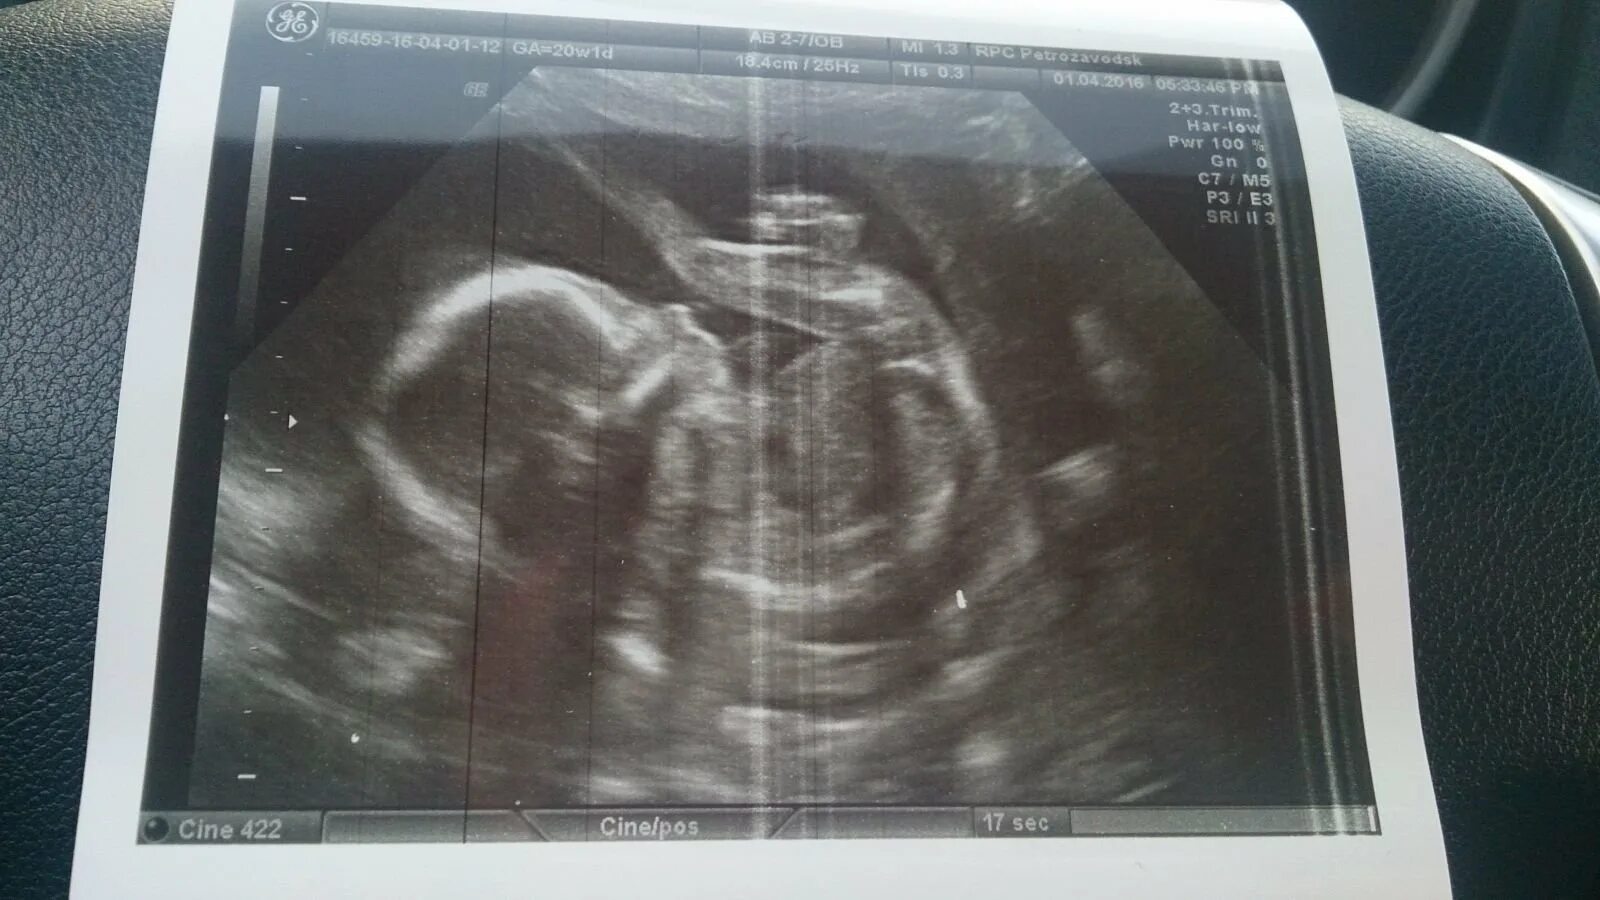

Через 20 недель